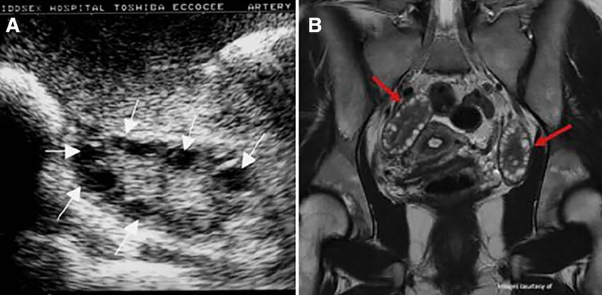

Untuk menegakkan diagnosis PCOS, dokter akan melakukan serangkaian pemeriksaan yang meliputi wawancara medis, pemeriksaan fisik, serta pemeriksaan penunjang. Salah satu pemeriksaan utama adalah USG transvaginal atau USG panggul untuk melihat apakah terdapat banyak kista kecil di ovarium (tanda khas PCOS). Biasanya akan tampak ovarium membesar dengan banyak folikel kecil yang tersusun di tepi, menyerupai “kalung mutiara”.

Jika hasil USG belum cukup jelas atau dibutuhkan evaluasi lebih lanjut, maka dokter dapat menyarankan pemeriksaan MRI pelvis, yang mampu memberikan gambaran anatomi organ reproduksi wanita dengan lebih detail. Gambaran PCOS pada MRI antara lain menunjukkan pembesaran ovarium bilateral dengan banyak folikel kecil berukuran <9 mm yang tersebar di tepi ovarium.

Gambar temuan PCOS dalam MRI3